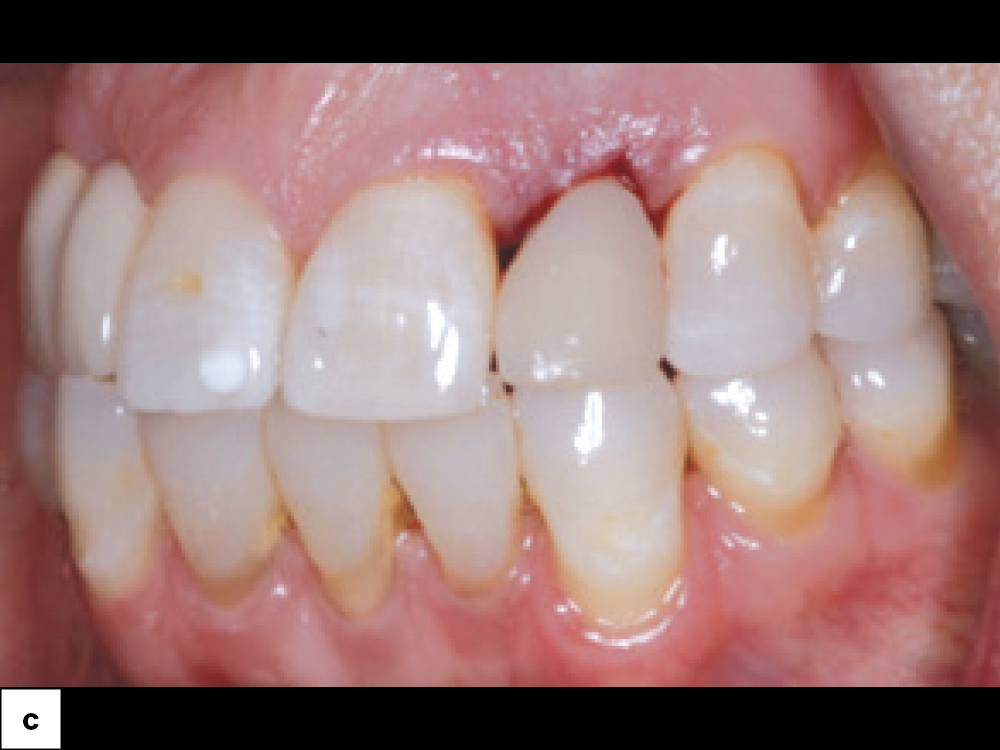

Extraction Site by Fenestration Case Pt2

Extraction Site by Fenestration Case Pt3

Extraction Site by Fenestration Cast Pt4

Extraction Site by Fenestration Cast Pt5

In this case example, an implant was immediately placed into an extraction site compromised by a fenestration. By utilizing the appropriate diagnostic, surgical and bone grafting techniques, a predictable restoration was delivered for the patient, and abundant bone volume was evident around the Hahn Tapered Implant.